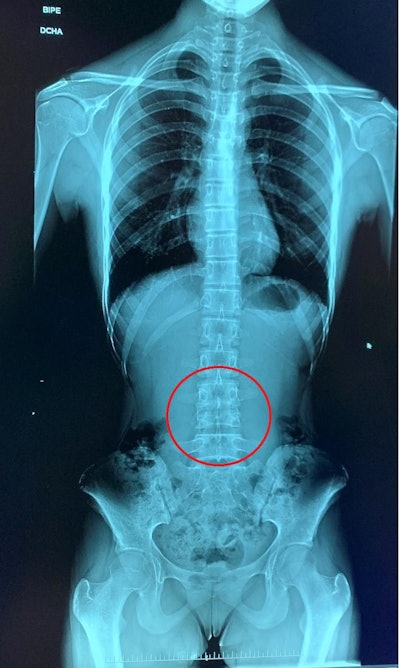

Reconstruction artifact in which a shift in part of the spine is shown. All figures courtesy of P. Garcia Castañon, S. Honorato Hernandez, C. Prieto Martin et al and ESR EPOS database.

A more subtle stitching artefact is shown, where two vertebrae seem to be united.